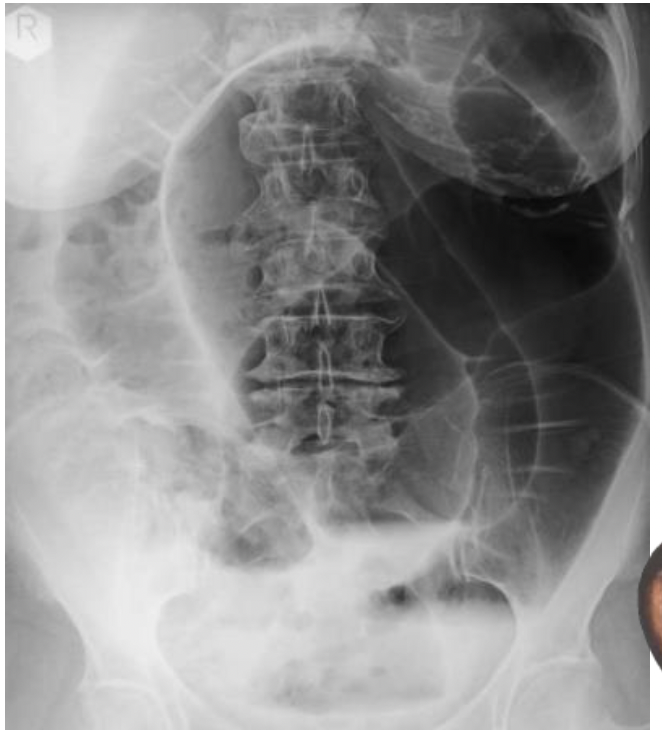

איך מבדילים בין המעי הדק לגס בצילומי בטן?

המעי הגס הוא פריפרי ויש לו האוסטרות, הן לא חוצות את כל המעי לרוחב.

במעי הדק לעומת זאת רואים פסים לבנים שחוצים את המעי מדופן לדופן.